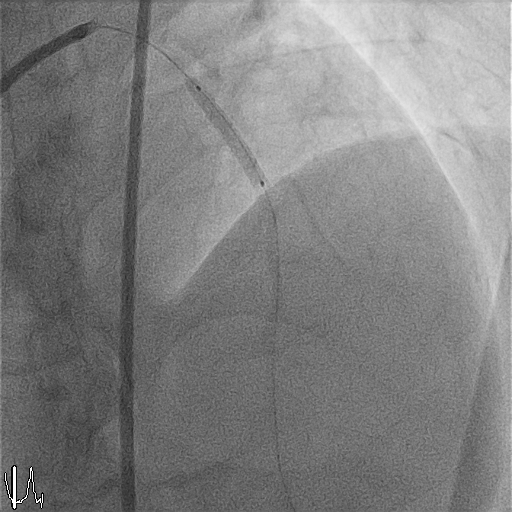

Pre-dilatation was performed with an IKAZUCHI ZERO 2.5 ¡¿ 15 mm balloon at 9–12 atm. Given the massive thrombus burden and prior incomplete systemic streptokinase infusion, intracoronary streptokinase was administered via the aspiration catheter in 1-mL aliquots (15,000 IU each), slowly over 1–2 minutes per dose, to a total of 150,000 IU. Progressive improvement in thrombus dissolution was observed with restoration of distal flow.Following thrombus resolution, direct stenting of the proximal LAD was performed using a Xience PRO-A 3.0 ¡¿ 23 mm drug-eluting stent, deployed at 9 atm. Post-dilatation was performed with a CONQUEROR NC 3.0 ¡¿ 15 mm balloon at 12–20 atm achieving full stent expansion. Final angiography demonstrated TIMI 3 flow with no dissection or residual stenosis.Given reduced LV systolic function, an IABP was inserted via the right femoral artery for hemodynamic support. Total contrast volume was 120 mL, total fluoroscopy time 10.03